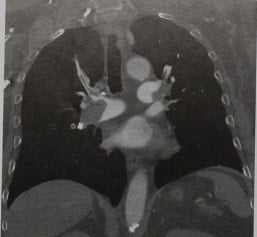

(а) Женщина 52 лет с жалобами на одышку, хрипы и отечность лица в течение трех недель. При рентгенографии органов грудной клетки в ПП проекции в верхней доле правого легкого определяется участок консолидации гетерогенной структуры. Также в правой паратрахеальной области выявляется объемное образование, распространяющееся на область шеи

(б) У этой же пациентки при КТ с контрастным усилением на реконструкции в коронарной плоскости в средостении визуализируется крупное инфильтративное объемное образование, которое циркулярно прорастает задние отделы дуги аорты правую легочную артерию и ее ветви. КТ с контрастным усилением является методом выбора для оценки инвазии сосудов опухолью.